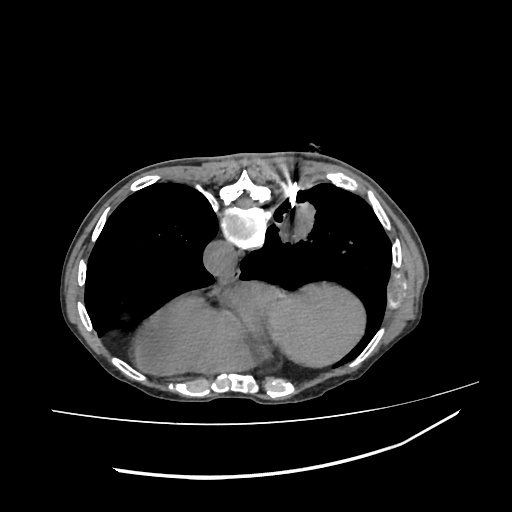

LUNG MASS BIOPSY, 70Y F